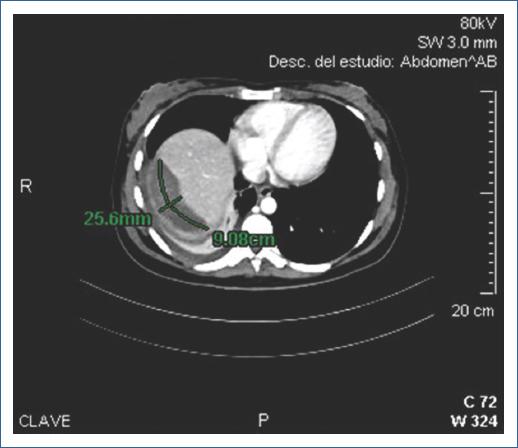

Paciente de sexo femenino de 27 años, con antecedente de colecistectomía laparoscópica un año antes. Ingresó por urgencias con cuadro de colangitis aguda leve, por lo que se realizó CPRE. Procedimiento efectuado por el médico adscrito asistido por residente; tiempo de canulación: 5 minutos, con cuatro intentos mediante guía hidrofílica. Se observaron múltiples úlceras con fibrina en el duodeno. Se identificó vía biliar intrahepática dilatada, colédoco de 10.41 mm con dos defectos de llenado (el mayor de 8.46 × 13.03 mm). Se realizó esfinterotomía a 12 mm y barridos con balón, con salida de dos litos y resolución completa de la coledocolitiasis. Cuatro horas después presentó taquicardia persistente y dolor epigástrico. La TC mostró hematoma hepático subcapsular subagudo de 235 ml, con burbujas de aire y zonas de densidad heterogénea (Fig. 3). Fue intervenida quirúrgicamente de urgencia: se identificó hematoma subcapsular hepático roto post-CPRE (WSES grado IV, AAST grado III), tratándose mediante drenaje y empaquetamiento hepático, con reintervención para desempaquetamiento. Requirió antibioticoterapia y transfusión de dos paquetes globulares. Egresó a los 13 días con evolución satisfactoria.